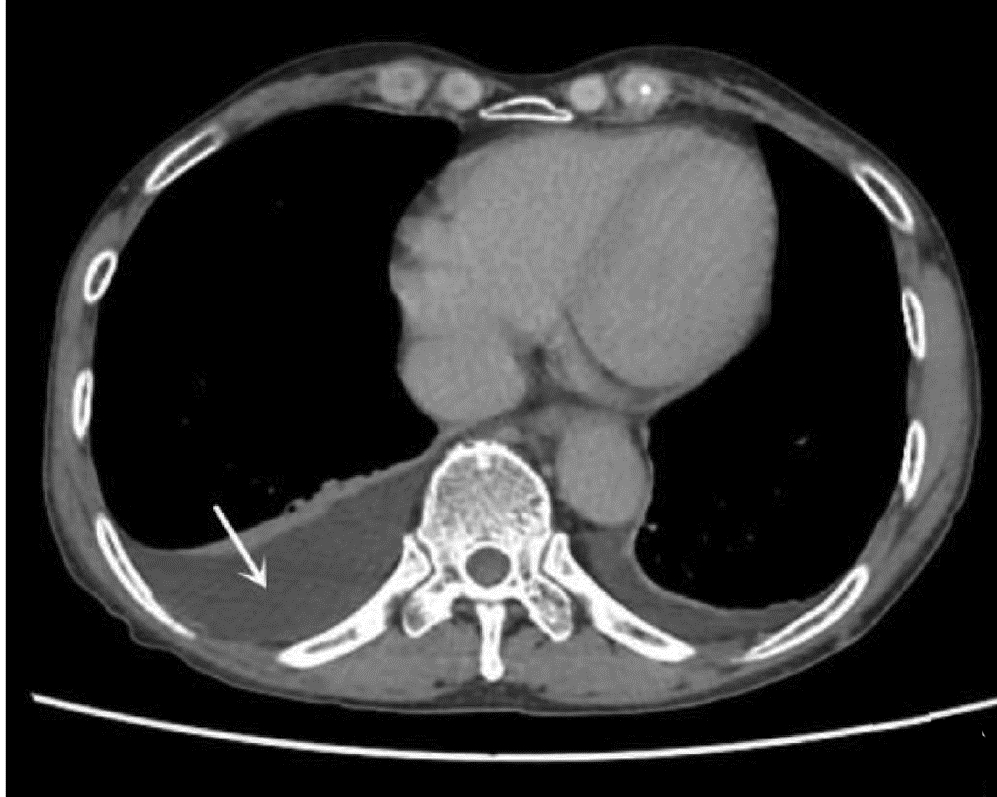

Brain abscess secondary to liver abscess in type 2 diabetes mellitus: A case report

Deyun WANG, Ruirui JIN, Zhen ZHAO, Hui LI

2022, 38(6): 1375-1376. DOI: 10.3969/j.issn.1001-5256.2022.06.031

Abstract(963) HTML (281) PDF (1890KB)(70)

Abstract: